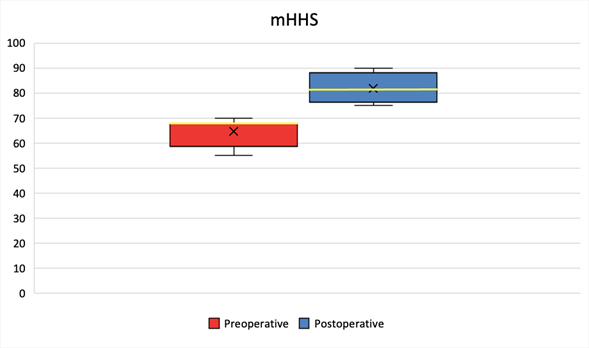

A total of twelve patients (15 hips), who met the required criteria were chosen for GM repair. All of them were women with an average age of 56.66 years (42-70). The mean follow-up period was 11 months (4-24). The demographic data is illustrated in Table 1. The median mHHS improved from 68 points (interquartile range [IQR], 59, 68 points) preoperatively to 82 points (IQR, 76, 88 points) at the latest follow-up (p=0.001) Table 2, Graphic 1. According to the mHHS score, 7% obtained excellent results (>90), 67% had good results (80-89), 26% fair results (70-79), and 0% had poor results (<70) Graphic 2. The median iHOT-12 score also improved from 70 points (IQR, 60, 80 points) preoperatively to 83 points (IQR, 82, 88 points) at the latest follow-up (p=0.001) Table 2, Graphic 3. There was a significant improvement (p<0.001) in the median VAS score in the total sample from 6 (IQR, 6, 7) preoperatively to 2 (IQR, 2, 5) postoperatively Table 2, Graphic 4. At the latest follow-up, 8 (66%) patients reported being very satisfied, 4 (33%) satisfied. During follow-up, there were no complications related to the surgical procedure. In the 3-month MRI study, all patients showed healing of the partial lesion of the GM tendon. Additionally, all patients presented a negative Trendelenburg test at the end of postoperative follow-up.

Graph 1 mHHS preoperative and postoperative outcomes.

The median mHHS was 68 points (IQR, 59, 68 points) preoperatively and 82 points (IQR, 76, 88 points) postoperatively. The x indicates the mean, the yellow line indicates the median, the box indicates the IQR, and the whiskers indicate the range.